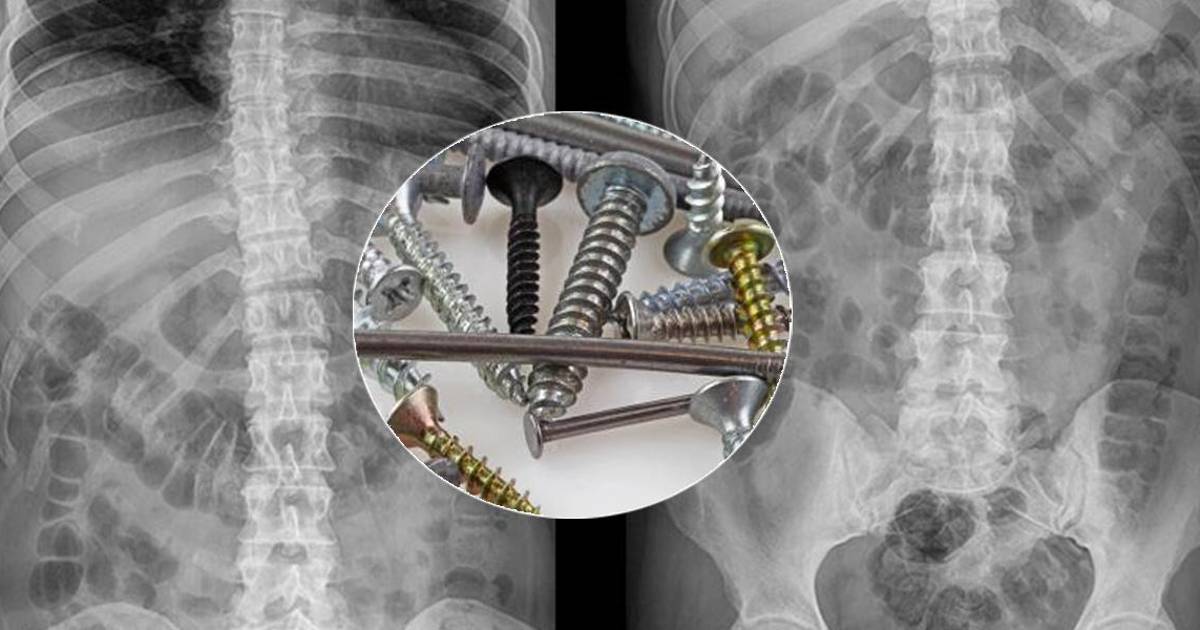

Médicos lituanos informaron este viernes que encontraron un kilogramo de clavos y tornillos dentro del estómago de un hombre que empezó a engullir objetos metálicos tras dejar de beber alcohol.

El hombre, cuya identidad no fue revelada por confidencialidad médica, fue ingresado con graves dolores abdominales en un hospital en la localidad de Klaipeda, en el litoral del mar Báltico.

Una radiografía de su estómago mostró que en su interior había piezas metálicas de hasta 10 centímetros.

“Durante las tres horas de operación (...), se sacaron todos los objetos externos, incluidos los más pequeños, del estómago del paciente”, dijo el cirujano Sarunas Dailidenas.

El hospital transmitió a medios locales una fotografía de una bandeja quirúrgica con los clavos y tornillos.

Nunca habíamos visto nada parecido”, aseguró a la prensa Algirdas Slepavicius, jefe del servicio de cirugía del hospital de Klaipeda.

Este doctor explicó que el paciente empezó a tragarse objetos metálicos tras haber dejado de tomar alcohol el mes pasado.

Añadió que, después de la operación, el estado de salud del paciente era estable.